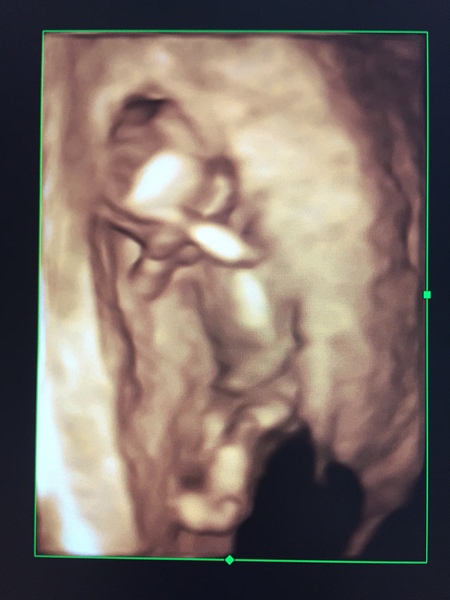

I've had another look at the 3D scan from last week (13 weeks) and it looks to me to be horizontal! What do you guys think?

Or is that just the umbilical cord? I can see why it's not relied on as an exact science!